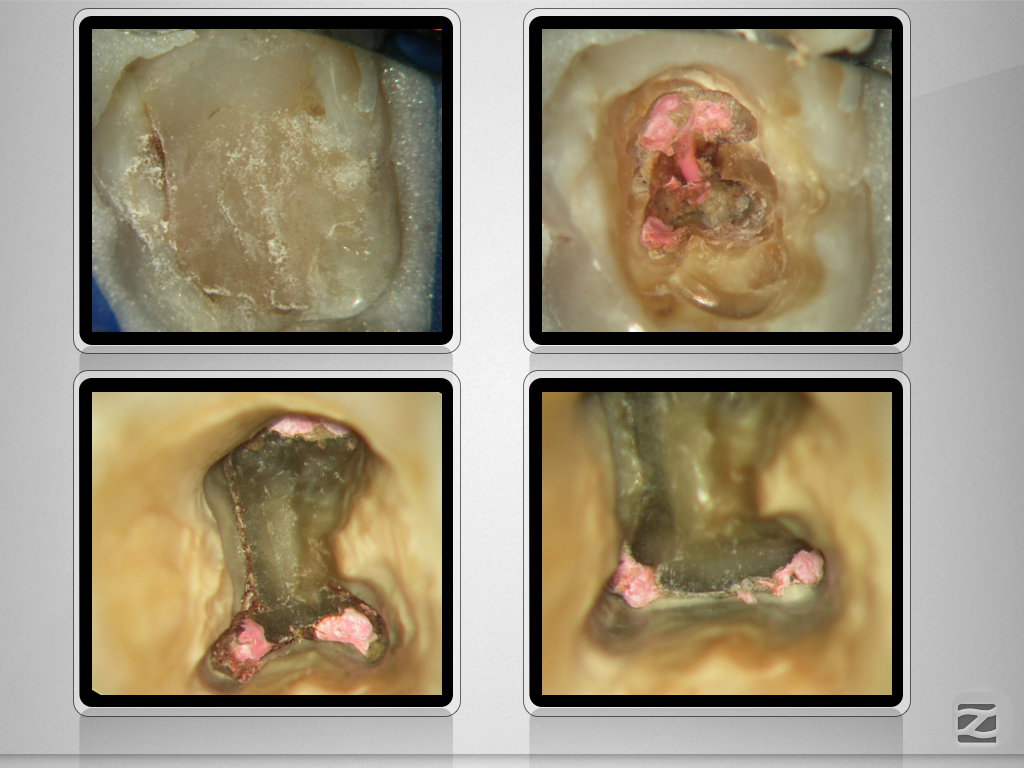

37D.011

Ausgedehnte apikale Lyse